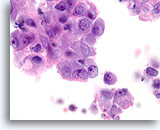

Atypische proliferatieve ductale laesie, Borst FNA, ThinPrep®.

Atypische kenmerken omvatten de licht discohesieve ductale populatie (let op afzonderlijke ductale cellen), de aanwezigheid van een stratificerende populatie ductale cellen zonder een duidelijke bijmenging met myoepitheliale cellen en de nagenoeg afwezigheid van gedeelde polariteit tussen de ductale cellen.

Atypische proliferatieve ductale laesie, Borst FNA, ThinPrep®.

Atypische kenmerken omvatten de licht discohesieve ductale populatie (let op afzonderlijke ductale cellen), de aanwezigheid van een stratificerende populatie ductale cellen zonder een duidelijke bijmenging met myoepitheliale cellen en de nagenoeg afwezigheid van gedeelde polariteit tussen de ductale cellen.